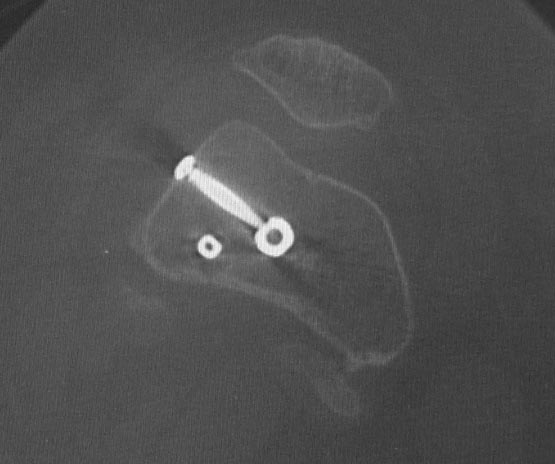

Уважаемые коллеги. Хотелось бы выслушать мнения и советы по представленному случаю. Пациент 42 лет, вес 130 кг, рост около 160 см, сахарный диабет в легкой форме (впервые выявлен после травмы). Травма в феврале 2011 г. - упал с мотоцикла на отдыхе за рубежом. По возвращении в Россию был прооперирован в несколько этапов: в марте 2011 г. - остеосинтез обеих костей правого предплечья пластинами по поводу открытого перелома; интрамедуллярный остеосинтез правого бедра; остеосинтез проксимального конца правой большеберцовой кости. В апреле 2011 г. был доставлен 1 блокирующий винт в дистальное отверстие гвоздя и выполнена пластика крестообразных и наружной боковой связок левого коленного сустава. В феврале 2012 г. были удалены фиксаторы с проксимального конца правой большеберцовой кости и выполнена пластика крестообразных и наружной боковой связок правого коленного сустава. За это время пациент смог начать ходить, сначала с костылями, а затем - без дополнительной опоры. Летом 2013 г. решил укрепить ноги с помощью подъемов пешком на пятый этаж. В результате - усталостная рефрактура правого бедра и перелом интрамедуллярного гвоздя. 09.09.2013 - реостеосинтез латеральным бедренным гвоздем с пластикой костной аутостружкой + СhronoS. Сейчас, через 6 мес после операции, может ходить без дополнительной опоры, периодически беспокоит болезненность в области правого бедра. На сегодняшних КТ - отсутствие признаков консолидации. Нужно ли что то делать и, если да, то что? Рассматриваемые варианты: повторная костная пластика дефекта; доставить блокирующие винты (самый проксимальный винт был удален через 3 мес после операции). Еще раз менять гвоздь не хотелось бы. На представленных снимках: бедро в 2011 г., через несколько мес после операции; в 2012 г., на стадии консолидации; со сломанным гвоздем; сразу после повторной операции (3 рентгенограммы). Все КТ - сегодняшние. Заранее спасибо за ответы.

Второй гвоздь был на 2 см длиннее и на 1 номер толще предыдущего. По-моему десятка.В принципе какая разница? Впечатление о том, что тонковат, ведь не зависит от реальной толщины гвоздя. Канал не рассверливал. Но забивал с трудом.

ждать-не ждать? Срочности нет, подождать можно, но активно, т.е. оценить клиническую и рентгенологическую динамику: два месяца назад, сейчас и еще через пару месяцев. Уменьшатся боли, появится более убедительная мозоль - ждите и наблюдайте дальше. Отсутствие положительной динамики можно приравнять к отрицательной динамике. Очевидно, что здесь имеют место быть обе проблемы: биологическая -мозоль слабая и механическая - тонкий гвоздь, недостаточная стабильность. Тогда -удаление, рассверливание (очень аккуратное, по 0.5 мм шаг, острыми фрезами, чтобы не пожечь кость - кортикал толстый и довольно прочный). Для 130 кг диаметр гвоздя минимум 12 мм, лучше больше. Здесь можно и 14мм гвоздь взять и блокировать дистально винтами 6,0 мм. Открывать перелом и пытаться делать еще пластику экстрамедуллярно не стоит. Рассверливания будет достаточно.

Согласен, стержень тонковат в дистальном отломке. Если совсем никак не возможно перепровести с рассверливанием более толстый стержень, можно согласиться с вашим предложением ввести еще один винт в дистальный конец гвоздя, но полностью убрать винты из проксимального отломка, чтобы перенести осевую нагрузку на кость и не опасаться перелома гвоздя или винтов.

Насколько это эффективно в отношении консолидации будет видно примерно через 6 недель. Незабудьте сделать, если его нет, обычный свежий снимок до динамизации для последующего сравнения.

Источник проблем - отсуствие рассверливания, тонкий гвоздь и костная пластика. При интрамедуллярном остеосинтезе (относительная стабильность) класть кусочки кости открыто бесполезно - не приживут. Только еще ухудшили кровоснабжение концов. А что там с длиной сегмента? Если длина не потерялась - реостеосинтез с рассверливанием, как А.Семенистый написал. Если укорочение - удалить, остеотомия на другом уровне и дистракиця, на стыке - компрессия, и по достижении нужной длины - заштифтовать с рассверливанием, аппарат снять только после запирания гвоздя.